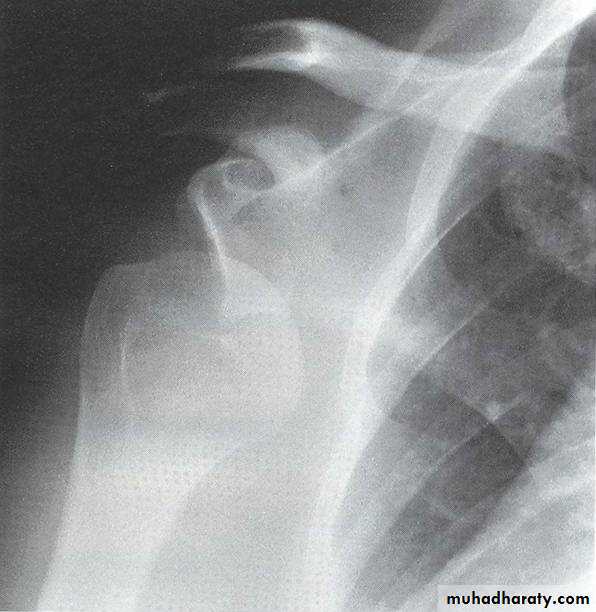

XR

AP

Scapular lateral

Axillary lateral

AP electrical bulb sign